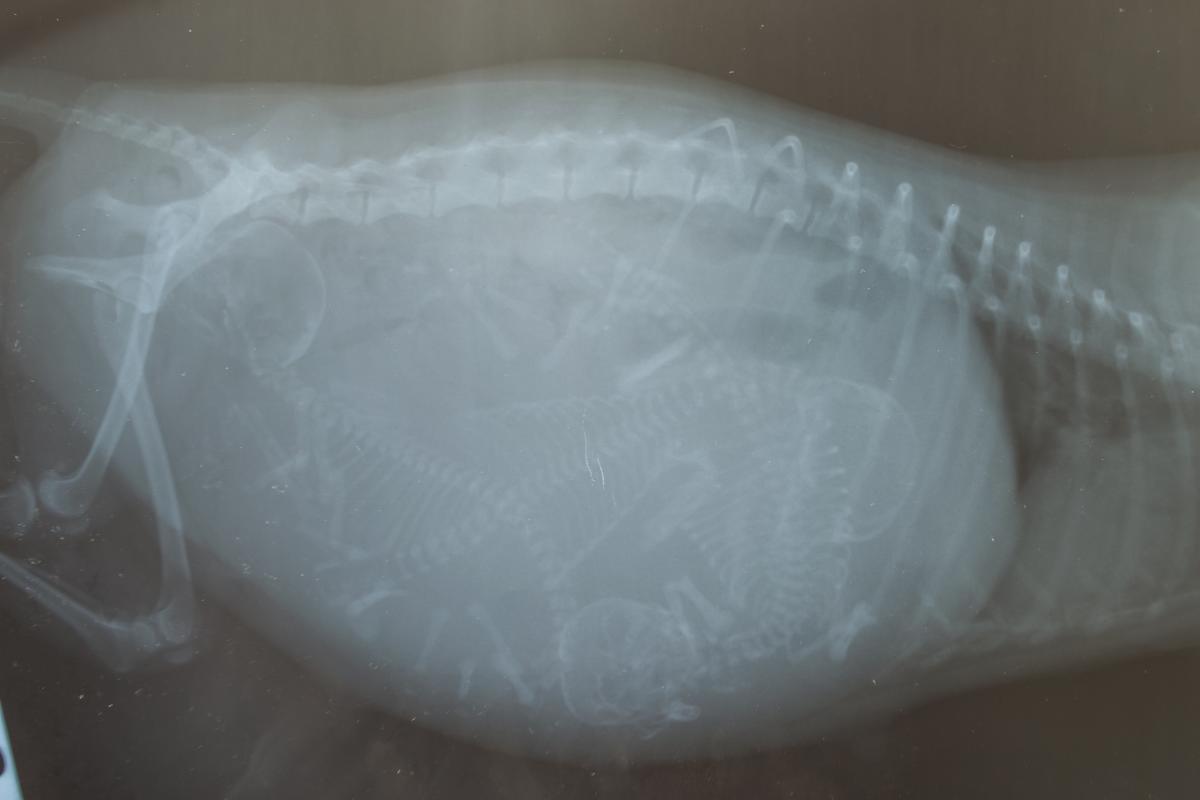

Finalmente, otro síntoma de parto de una perra decisivo es la aparición de las contracciones. Dichas contracciones uterinas permitirán la salida de los cachorros. Ahora bien, ¿cómo saber si mi perra tiene contracciones? Son fáciles de observar pues si mantienes la atención en el vientre de tu perra verás que este se mueve rítmicamente, también pueden expresar signos de dolor, los cuales en este contexto son completamente normales.